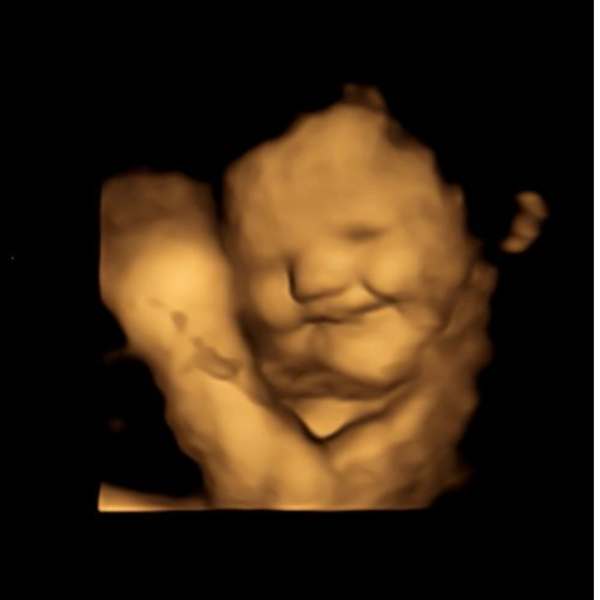

அதில் விரும்பிய உணவை தாய் உண்ணும் போது, சிசுக்கள் சிரித்த முகத்துடனும், பிடிக்காத உணவை உண்ணும் போது சிசுக்கள் தங்கள் முகத்தை அஷ்டக்கோணலாகவும் மாற்றுவதை மருத்துவர்கள் வீடியோ பதிவு செய்துள்ளனர்.

பின்னர் 20 நிமிடங்கள் கழித்து இந்தப் பெண்களின் வயிற்றில் உள்ள சிசுக்களை 4D ஸ்கேன்களை கொண்டு விஞ்ஞானிகள் பார்த்தனர். அப்போது கேரட், பீட்ரூட், சப்போட்டா போன்ற இனிப்புச் சுவை மிகுந்த பழங்களை சாப்பிட்ட பெண்களின் சிசுக்கள் நன்றாக சிரித்துக் கொண்டும், ஜாலியாக அங்கும் இங்கும் அசைந்து கொண்டும் இருக்கின்றன. அந்த சிசுக்களின் முகத்தில் குறைந்தது அரை மணிநேரமாவது சிரிப்பு இருக்கிறது.

மேலும், வயிற்றில் இருக்கும் சிசுக்கள் தங்கள் உணர்ச்சிகளை காட்டும் புகைப்படங்களையும், வீடியோக்களையும் மருத்துவர்கள் வெளியிட்டனர். இந்த புகைப்படங்கள் சமூக வலைதளங்கில் வைரலாகி வருகின்றன.